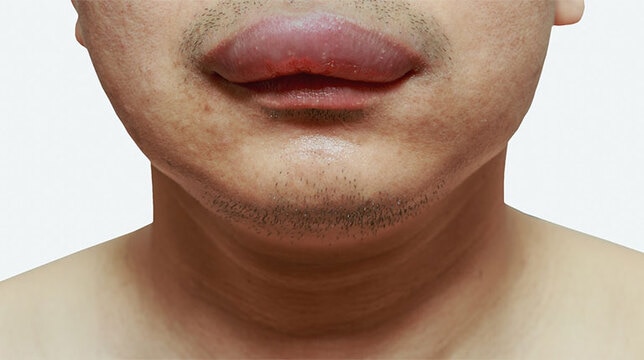

Tại sao môi bị sưng? Cách trị sưng môi nhanh nhất ngay tại nhà

Nguyên nhân môi bị sưng ngứa là do chấn thương va đập, môi sưng do dị ứng thời tiết, bị sưng môi do dị ứng thực phẩm, tự nhiên bị sưng môi trên do côn trùng cắn,...